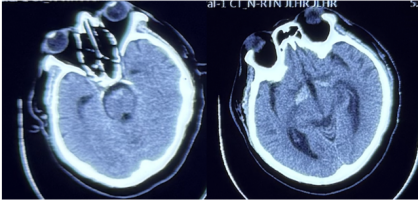

2024年9月22日,患者发热、头痛(当时甲泼尼龙减至40 mg qd口服),双下肢无力明显加重,伴有胡言乱语、精神异常。2024年9月27日,患者意识模糊,颈项强直;脑脊液:压力340 mmH2O,黄色浑浊,白细胞383*106/L,糖1.82 mmol/L↓,氯化物109.4 mmol/L↓,蛋白7.53 g/L↑,宏基因组学二代测序水痘-带状疱疹病毒(VZV)序列数3499,Xpert(-);头颅计算机体层摄影(CT)示幕上幕下脑积水;考虑脑疝,转入ICU行脑室外引流术,予以阿昔洛韦抗病毒、四联抗结核治疗,地塞米松抗炎。2024年10月3日,患者意识好转,头颅MRI示右侧顶枕叶点状、胼胝体压部DWI高信号,ADC减低。2024年10月10日复查腰穿脑脊液压力>400 mmH2O,黄色浑浊,蛋白5.8 g/L↑,白细胞247*106/L,糖7.42 mmol/L,氯化物108.5 mmol/L↓;腰穿后再次脑疝,留置脑室外引流。2024年10月29日转入普通病房,家属发现双耳听力下降,当地考虑中枢神经系统VZV感染、结核感染不除外,予以抗病毒、抗结核、脱水降颅压治疗约1个月,患者头痛好转,精神行为异常明显,双下肢肌力0级。2024年11月5日就诊于我院急诊,头颅增强MRI提示多发性脑梗死(图2)、硬脑膜强化(图3);历次腰穿结果见表1。病来,患者精神、食欲、睡眠欠佳,留置尿管,辅助通便,体重无明显下降。

图2 头颅常规MRI+SWI

图3 头颅增强MRI

头颅CT:鞍上池、脚间池、桥前池蛛网膜下腔出血(图5)。

图5 头颅CT

第二阶段病程:大剂量激素冲击治疗后出现发热、头痛、精神行为异常,腰穿脑脊液白细胞明显升高,考虑免疫抑制后继发感染性脑膜脑炎。脑脊液宏基因组学二代测序VZV序列数高,经抗病毒治疗后颅压、白细胞、蛋白及VZV序列数均明显下降,支持中枢神经系统VZV感染。此外,患者脑脊液蛋白显著升高,糖、氯化物降低,血结核感染特异性T细胞检测阳性,影像上脊膜增厚明显,需考虑合并中枢神经系统结核感染不除外。患者多发性脑梗死、局部蛛网膜下腔出血,颅内动脉多发节段性中重度狭窄,需考虑合并感染性血管炎可能。治疗方面,予以足量、足疗程抗病毒治疗及抗结核治疗。